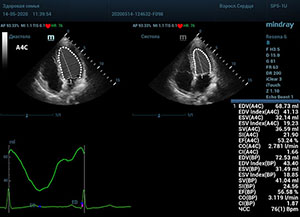

Что могут предложить современные приборы? Приборы нашего времени являются мощными вычислительными машинами, способными обрабатывать полученную информацию даже без помощи человека. Система автоматического вычисления фракции выброса – AUTO EF на приборах серии Resona компании Mindray сделает все за вас. За пару секунд прибор сам отыщет нужную фазу сердечного цикла и произведёт измерение и расчеты, а также покажет график изменения объема в сердечном цикле. От Вас требуется только получить качественное 4С и 2С сечение. Впрочем, прибор всегда оставляет возможность коррекции, если доктор имеет свое мнение на расположение точек планиметрии или момента измерения по ЭКГ каналу.